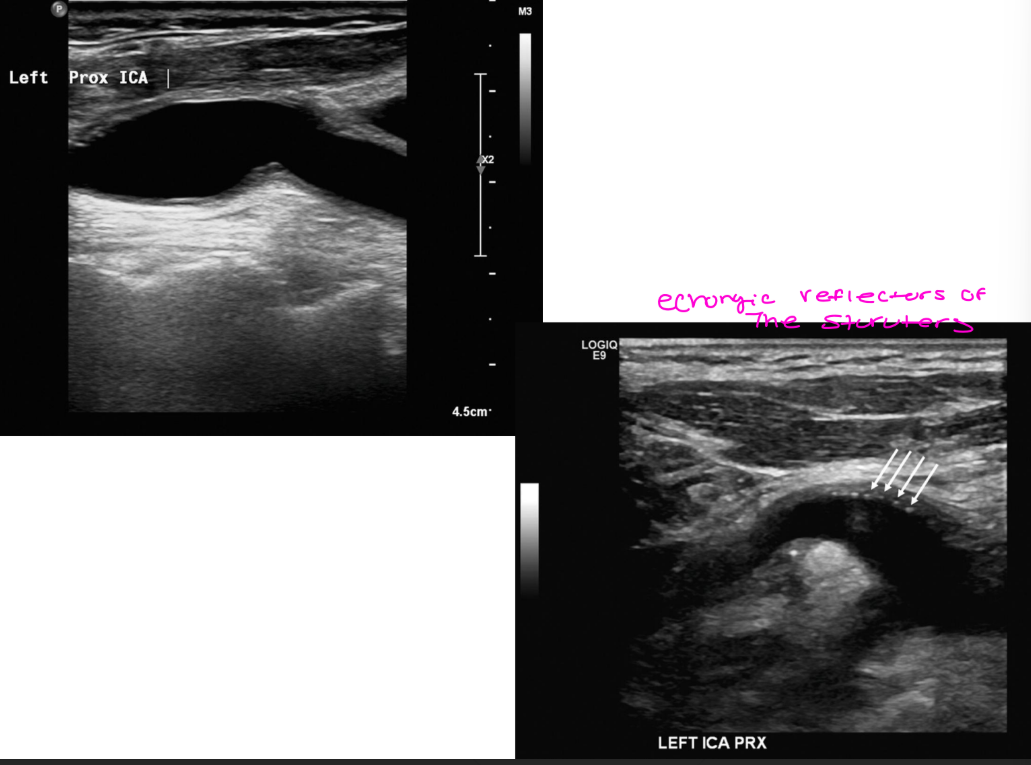

Endarterectomy sonographic appearance

what layers do you not see?

sutures can appear how?

wall thickening can occur-2 types

doppler appearance how

Sonographic appearance

Absent intima / media stripe

Sutures can appear as echogenic

reflector

Wall thickening can occur

Intimal hyperplasia

Re-stenosis can occur

Doppler appearance

Color – disturbed/flow

separation

Spectral – low velocity, disturbed

waveform